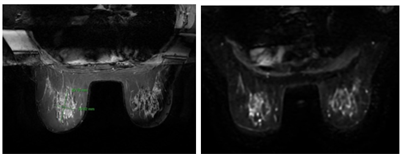

Ung thư trực tràng là một trong những ung thư tiêu hóa thường gặp, với chiến lược điều trị dựa trên giai đoạn bệnh, vị trí u (tính từ rìa hậu môn), nguy cơ xâm lấn mạc treo trực tràng và tình trạng...